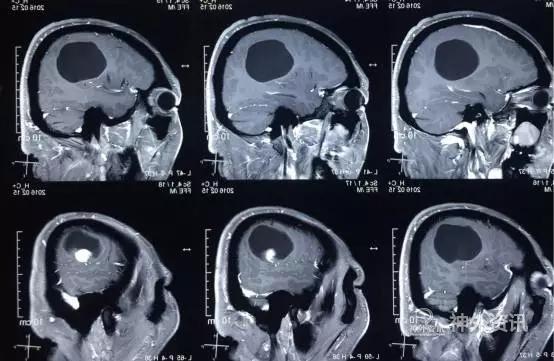

术后患者恢复良好,神志清,精神佳,四肢肌力V级,肌张力正常,病理征(-)。术后CT(图5)MRI(图6)未见血肿,肿瘤全切。

图5. 术后2小时CT。

图6. 术后48 小时 MRI (增强)。